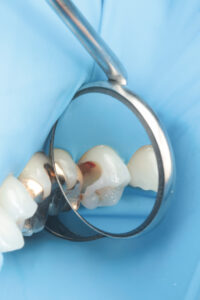

虫歯が深くても、神経を残せる可能性があります!

✅ 神経が露出しても諦めない保存処置

✅ 再発リスクを抑える精密治療

✅ 自費治療ではラバーダム防湿を徹底(無菌的処置)

「神経を抜くしかない」と言われた場合でも、保存できるケースがあります。大切な歯を守るためのベストな選択肢を一緒に考えましょう。